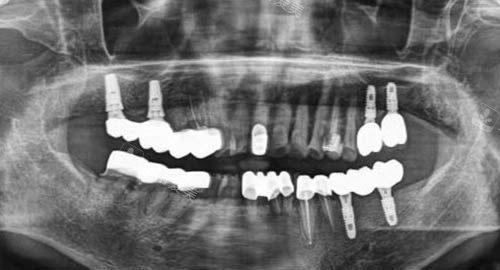

多颗牙齿种植ct

另一方面,医院采用靠前的种植技术,如智能化种植技术,通过计算机模拟种植过程,比较准定位种植体的位置和深度,大大提高了种植的成功概率,减少了手术创伤和患者的修复时间。

靠前的设备是基础,如口腔 CBCT 能够提供高清晰度的三维影像,帮助医生比较准了解患者口腔的内部结构。